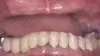

Before: Patient needs Upper and Lower Arch Rehabilitation. After: Great smile, chewing function, and facial tissue support

Before: Patient needs Upper and Lower Arch Rehabilitation. After: Great smile, chewing function, and facial tissue support possible with an Upper Denture that is supported with Implants and Lower Implants and Crowns.